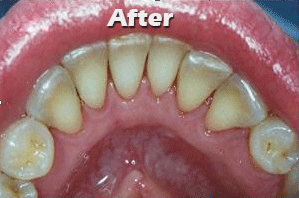

1. Scaling and polishing of teeth:

Scaling is done to remove the plaque and calculus accumulated around the teeth. This is necessary for the regular maintenance of a healthy dentition.